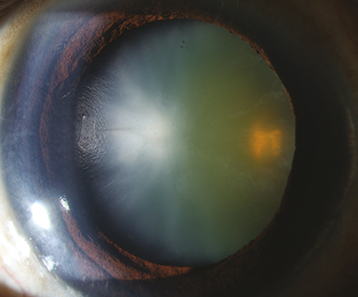

(See Figure 13.1.1.)

Figure 13.1.1: Cataract with early cortical changes and nuclear sclerosis.

Opacification or discoloration of the normally clear crystalline lens.